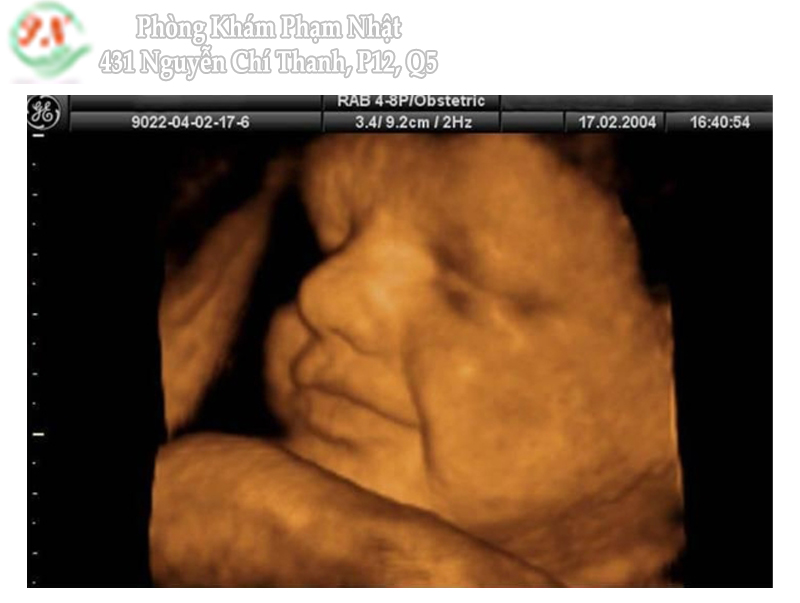

Nuchal translucency – NT tạm dịch là khoảng sáng sau gáy hay mờ da gáy

Là hình ảnh trên siêu âm của lớp tụ dịch dưới da vùng cổ thai nhi chỉ quan sát rõ khi thai ở thời điểm từ 11 đến 13 tuần 6 ngày.

Khi NT dày thường đi kèm với bất thường nhiễm sắc thể. Bất thường hay gặp nhất là bất thường nhiễm sắc thể 21.

Theo thống kê, trong 75-80% các thai bị trisomy 21 có NT dày > 95% giá trị bình thường của tuổi thai.

NT dày ngoài là biểu hiện của bất thường NST. Đây còn là biểu hiện của bất thường tim thai bẩm sinh hoặc biểu hiện của phù thai trong bệnh cảnh nhiễm trùng bào thai. Hay thiếu máu bào thai.